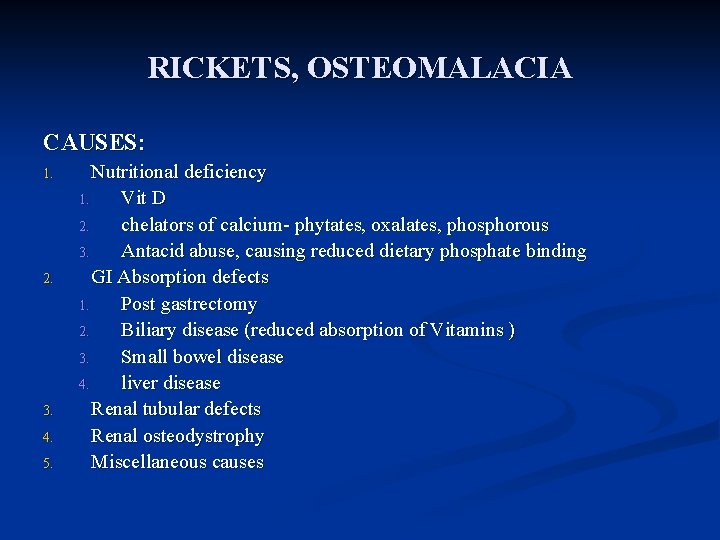

RICKETS, OSTEOMALACIA CAUSES: 1. 2. 3. 4. 5. Nutritional deficiency 1. Vit D 2. chelators of calcium- phytates, oxalates, phosphorous 3. Antacid abuse, causing reduced dietary phosphate binding GI Absorption defects 1. Post gastrectomy 2. Biliary disease (reduced absorption of Vitamins ) 3. Small bowel disease 4. liver disease Renal tubular defects Renal osteodystrophy Miscellaneous causes